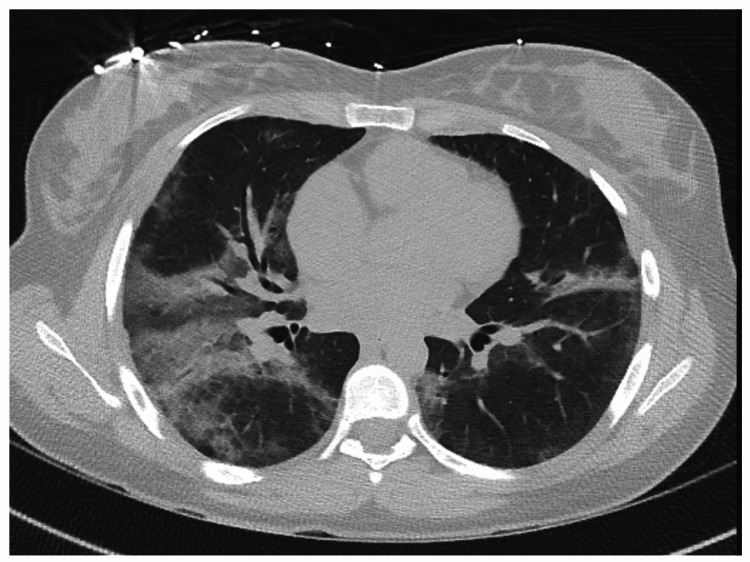

An 18-year-old woman with a medical history of obsessive-compulsive disorder and exercise-induced asthma presented with complaints of chest tightness and shortness of breath. The patient endorsed vaping and using marijuana daily for two years prior to admission. Vital signs on presentation included heart rate of 120 beats per minute, respiratory rate of 24 breaths per minute, and oxygen saturation of 93% on room air. Lung sounds were clear to auscultation. WBC count was 19.4 K/µL. CT chest showed patchy bilateral airspace GGOs (Figure 4) and no evidence of pulmonary embolism.

She was empirically started on ceftriaxone and azithromycin for CAP. Blood culture and sputum culture were negative, and workup for atypical infections was nondiagnostic. HIV test was negative. Considering the lack of clinical improvement and increasing oxygen requirements, antibiotics were broadened, and a repeat CT chest was done that showed waxing and waning of extensive bilateral GGOs.

She underwent bronchoscopy with BAL that showed neutrophilic and lymphocytic alveolitis (total WBCs of 782 with a differential of neutrophil 21%, lymphocyte 31%, monocyte 47%, and eosinophil 1%) with evidence of intra-alveolar macrophages (Figure 5). Cellblock from transbronchial biopsy revealed similar findings (Figure 6). Workup for fungal or mycobacterial pneumonia was negative. Antibiotics were stopped after seven days, and she was started on intravenous (IV) methylprednisolone with rapid resolution of symptoms. The patient was transitioned to oral prednisone, which was tapered over a course of 10 days.